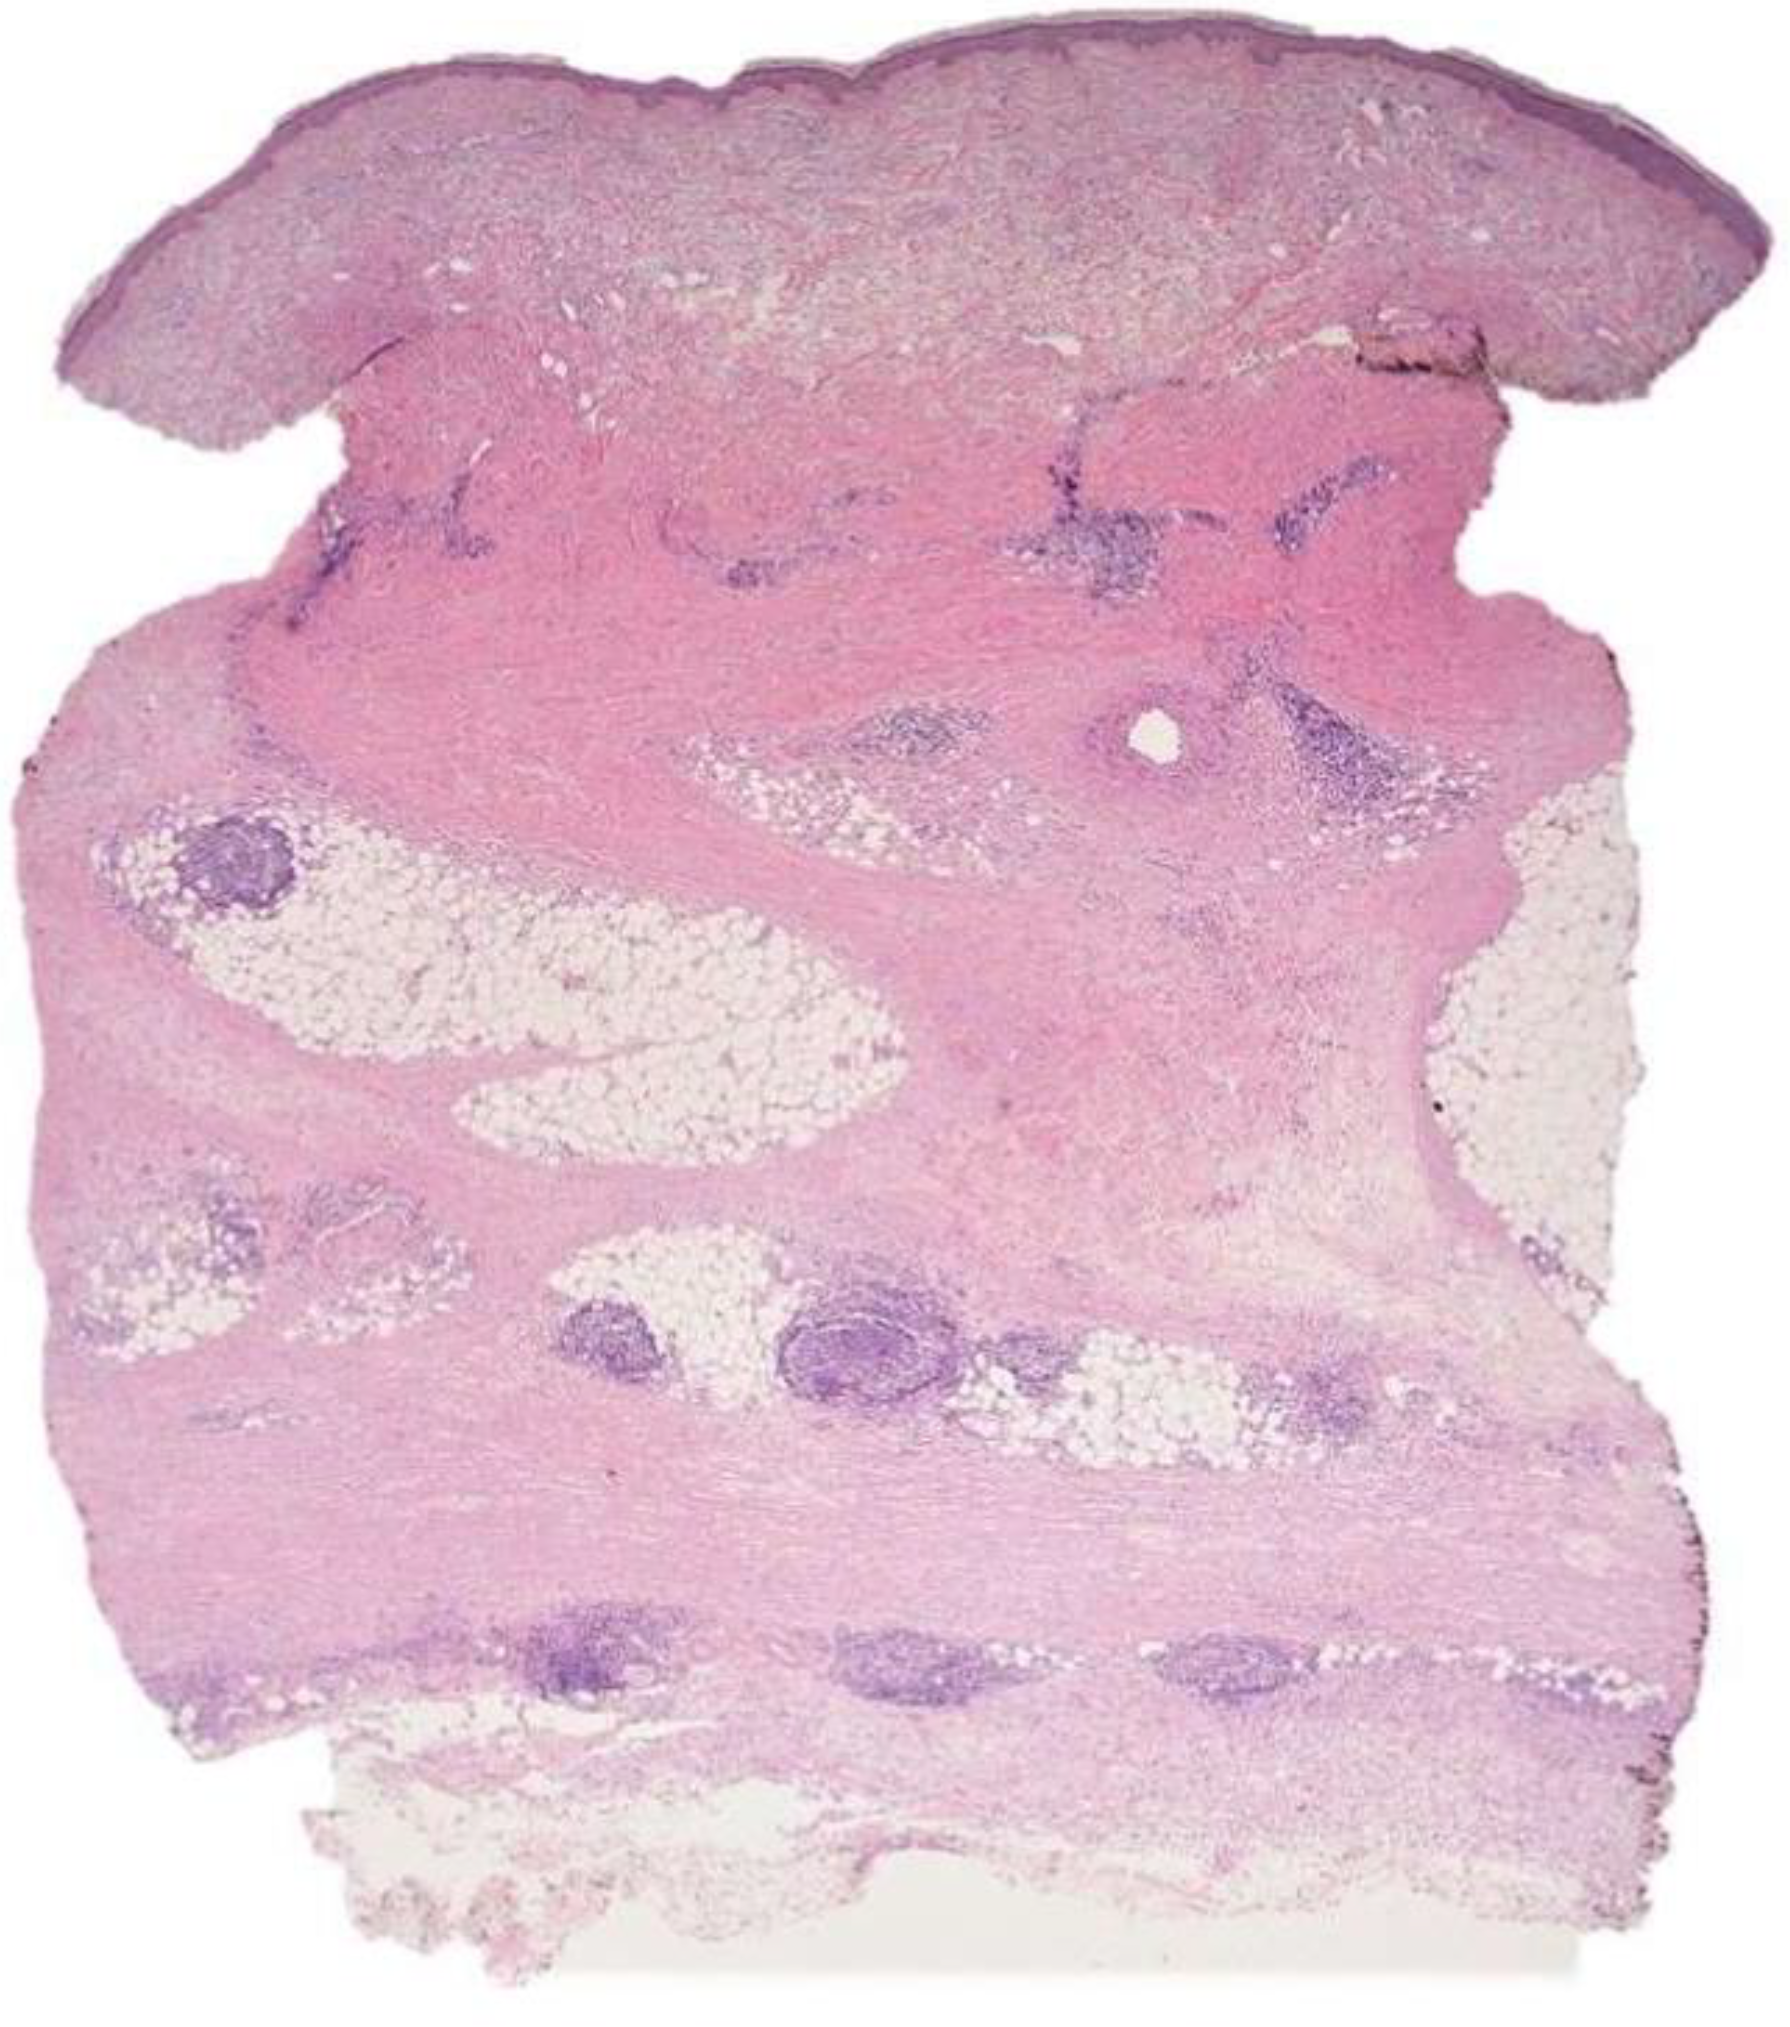

Morphea Profunda with Tertiary Lymphoid Follicles: Description of Two Cases and Review of the Literature

2.1. Case 1

2.2. Case 2